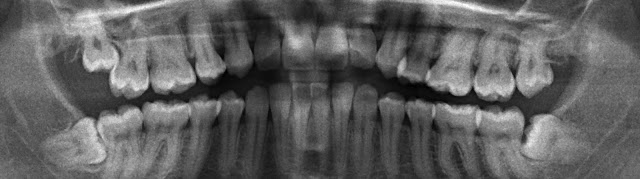

Idag när jag gick till tandläkaren trodde jag att jag skulle skrapa lite tandsten, konstatera att jag inte hade några hål och betala typ 500:- för det hela, som jag gör varje år när jag går till tandläkaren. Tyvärr blev det inte så. En liten dum visdomstand har nämligen stuckit fram sitt fula tryne på ett sätt att det är i princip omöjligt att komma åt och göra rent vilket har lett till ett hål (mitt första) med risk för spridning till nästa tand. För att utreda saken togs bilden ni ser ovan. Det här är en röntgenbild av mina tänder som tas genom att kameran snurrar runt hela huvudet. Den har jag betalat 970 DKK för och hela besöket slutade med att vara nästa tre gånger så dyrt som jag räknat med.